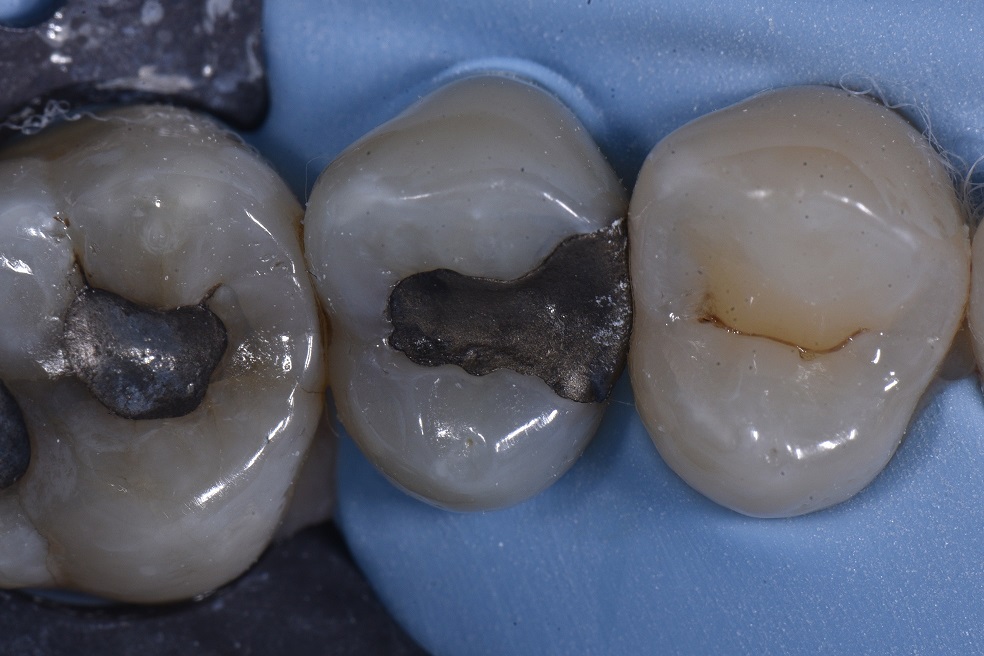

For those of you who got drenched getting to work, I feel for you. This case should hopefully make you feel better and fired up for the day. This was a replacement of an amalgam restoration as per the patient’s wishes – there were no radiographic signs of recurrent caries, but tenderness to biting pressure on this tooth. Removal of the amalgam was standard, and the restoration selectively etched using G-Premio Bond (GC) before using Flo-X A2 (the low viscosity flowable composite that I prefer to use to line the base of preparations) (GC). The proximal wall was perfectly contoured using a hermetically-sealed Garrison Composi-tight 3D XR matrix system used with Slick Bands. The restoration was layered using GC Essentia U (a 50:50 ratio of A2 and A3), which has just an outstanding chameleon effect.